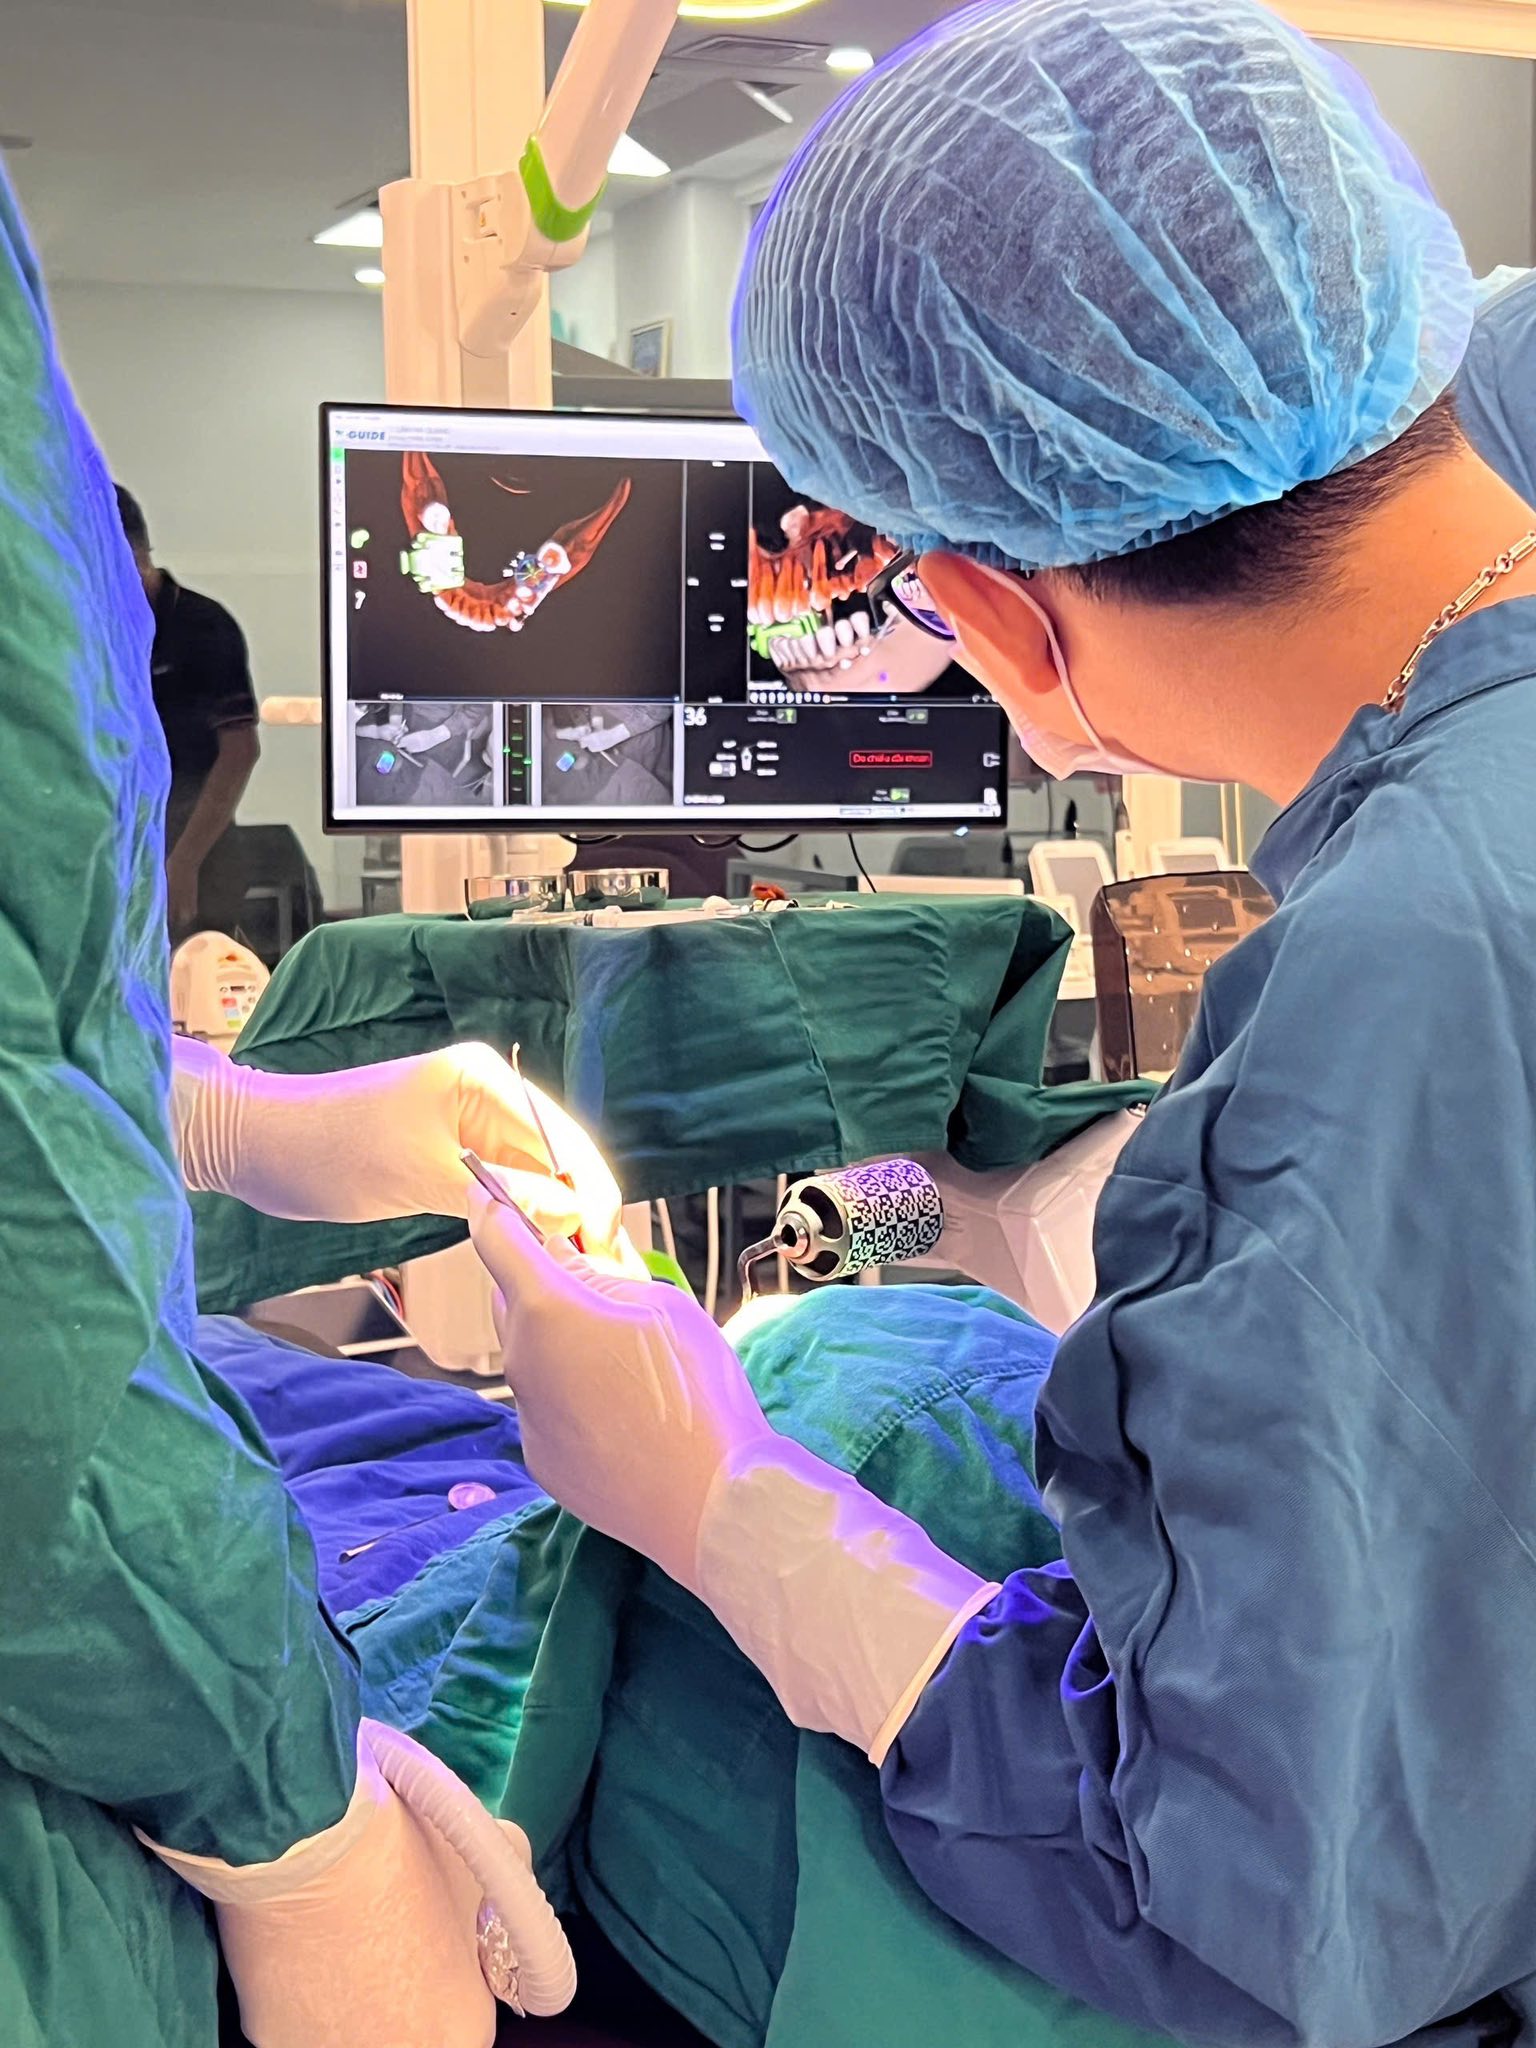

GPS CỦA NỤ CƯỜI – IMPLANT AN TOÀN, CHÍNH XÁC VỚI X-GUIDE

Trong nha khoa hiện đại, độ chính xác là chìa khóa quyết định thành công của một ca cấy ghép Implant. Và tại Nha khoa Như Ngọc, chúng tôi ứng dụng những công nghệ tiên tiến nhất để đảm bảo...